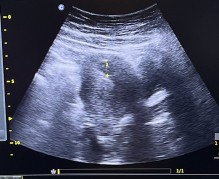

kantung bayi

Bun sy mau tanya, normalkah hamil 6 minggu baru kliatan kantung.a aja atau bagaimana ? Dan ukurannya baru 2cm bun, normalkah ?

Aku juga hamil 6w4d baru keliatan kantung nya aja bun, di suruh balik sebulan lagi sama dokternya

hamil 6 minggu ini tuh kantungnya mirip sama janin kecil yah . atau ini memang kantung saja bun ?